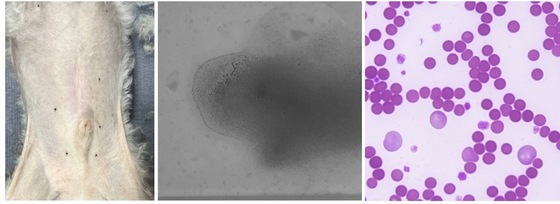

해당 반려견의 경우 신체검사에서 황달이 확인됐다. 혈액검사 결과 적혈구 용적률(HCT)이 11.9%로 측정됐다. 정상 범위인 37~55%의 절반에도 못 미치는 수치로 중증 빈혈 상태였다. 적혈구는 체내 산소를 운반하는 역할을 하기 때문에 급격히 감소하면 무기력, 식욕 저하, 호흡 곤란, 심박수 증가 등 전신 증상이 나타나며 응급 상황으로 이어질 수 있다.

또한 적혈구 파괴 시 생성되는 빌리루빈 수치가 상승하며 황달이 나타났고, 염증 수치 역시 높게 확인됐다. 혈액 도말 검사에서는 자가 응집 반응이 관찰돼 면역 체계가 적혈구를 공격하는 용혈 빈혈(용혈성 빈혈) 양상이 의심됐다.

황달이 확인된 반려견의 배(맨 왼쪽), 자가 응집 반응이 확인된 혈액, 현미경으로 확인했을 때 뭉치고 있는 적혈구(SD동물의료센터 제공) © 뉴스1